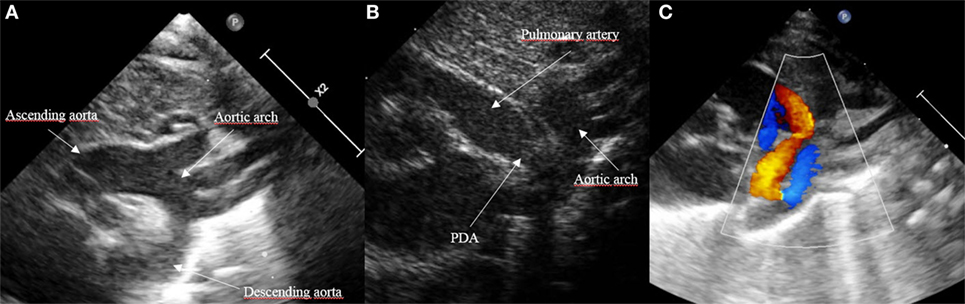

SSN

High basal PSAX

What views can a PDA be seen from (2)?

Patent ductus arteriosus

What is seen in this 2D image?